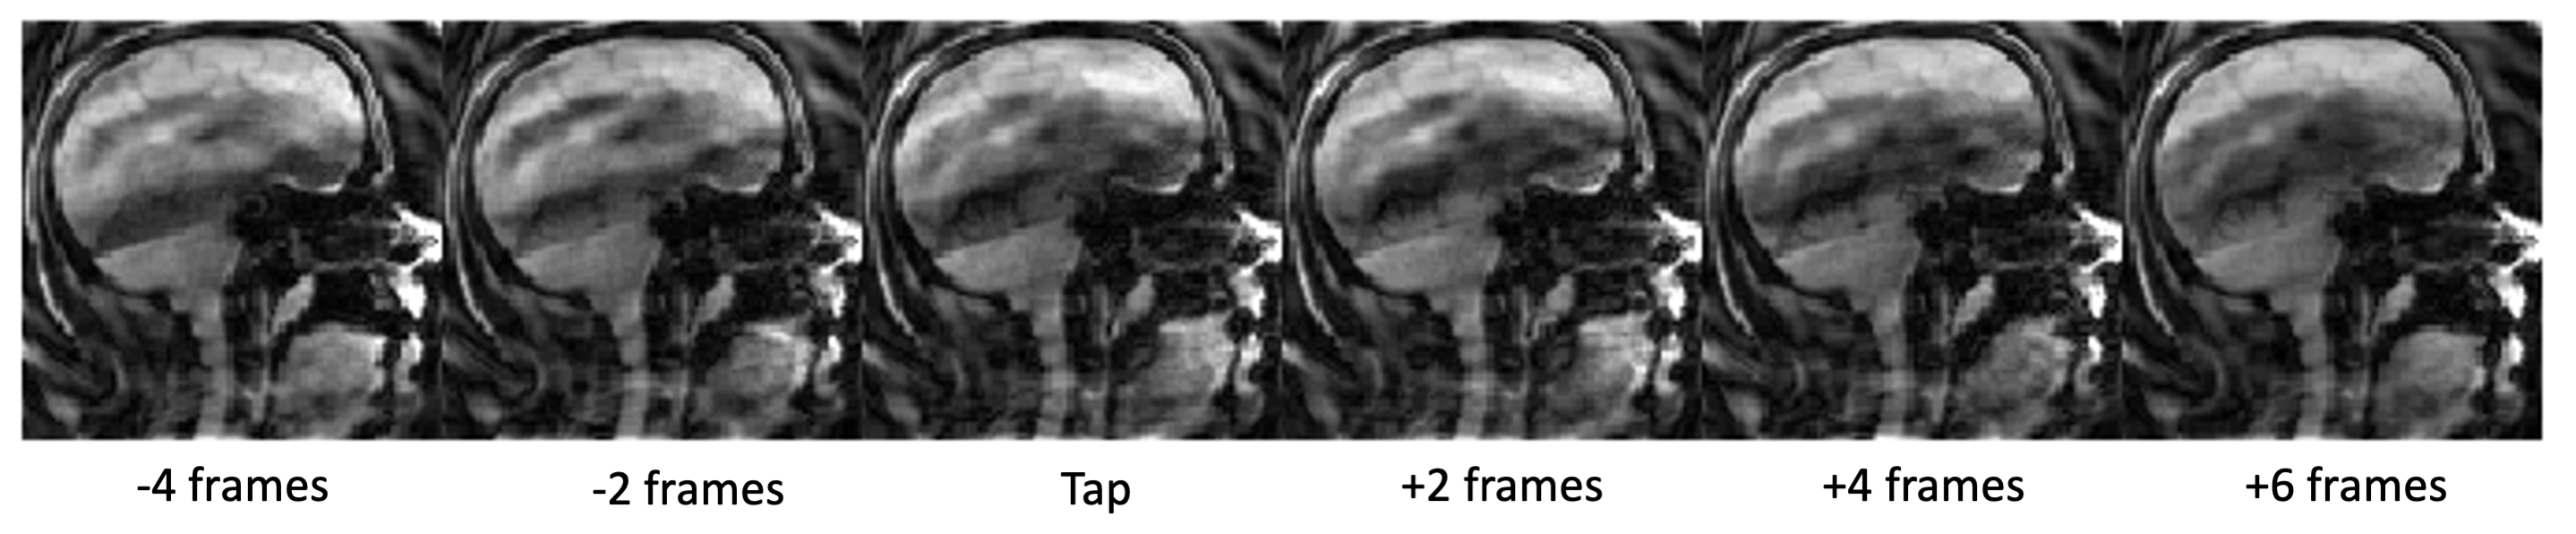

Figure 5: A) GLM derived activation maps from the tapping events identified from the dynamic scan. Activations include tongue areas along with a few motion-induced false activations. B)Task waveform from convolving tongue tapping events with hemodynamic response function.

Figure 3 shows a strip of images (skipping every other frame for better visualization of motion) right before, during, and after a tongue tap. The 10 frames comprise 766 ms of total time. In this figure, you can clearly observe the tongue elevate to the alveolar ridge (front part of roof of the mouth) and return to its resting position. In order to create a time series of activity for fMRI analysis, a pixel was placed near the point of contact for the tapping and the mean signal was filtered and detrended to make an indication of the tongue tapping, shown in Figure 4. Figure 4 also shows the time plot for a strip of pixels through the tongue tip, showing the tongue push forward and upward as it elevates. Using the timings from the taps identified from the dynamic time series, a functional MRI analysis was conducted using FEAT7 in FSL on the functional MRI images. Activation in the sensorimotor tongue region is shown in Figure 5, along with some spurious motion-related activations.